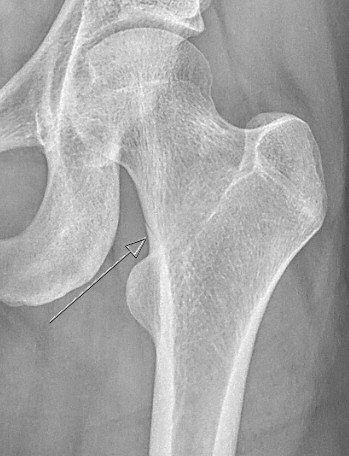

Exempel på stressfraktur i kollum femoris

Slätröntgen kan ge diagnos, men i tidigt skede finns ibland endast indirekta tecken såsom förtjockad kortex. MR eller scintigrafi ger tidig diagnos, ett alternativ kan vara förnyad röntgenundersökning efter 2-6 veckor.